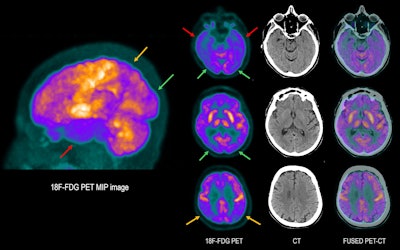

76-year-old woman with involuntary movements and tremors in the upper limbs, disorientation, and cognitive impairment (memory loss). Brain F-18 FDG PET scan shows significant decrease in cortical metabolism in the temporal lobes (red arrows) and parietal regions (yellow arrows), lobes that are usually affected both in dementia with Lewy bodies (DLB) and Alzheimer’s disease (AD). In this case, involvement of the occipital lobes is also seen (green arrows), which is not usually seen in AD. Cortical involvement is slightly asymmetrical, with the right side being more involved. A slight decrease in radiotracer concentration is also observed in the frontal lobes. The pattern of cortical metabolism involvement is compatible with DLB, also known as Lewy body dementia.